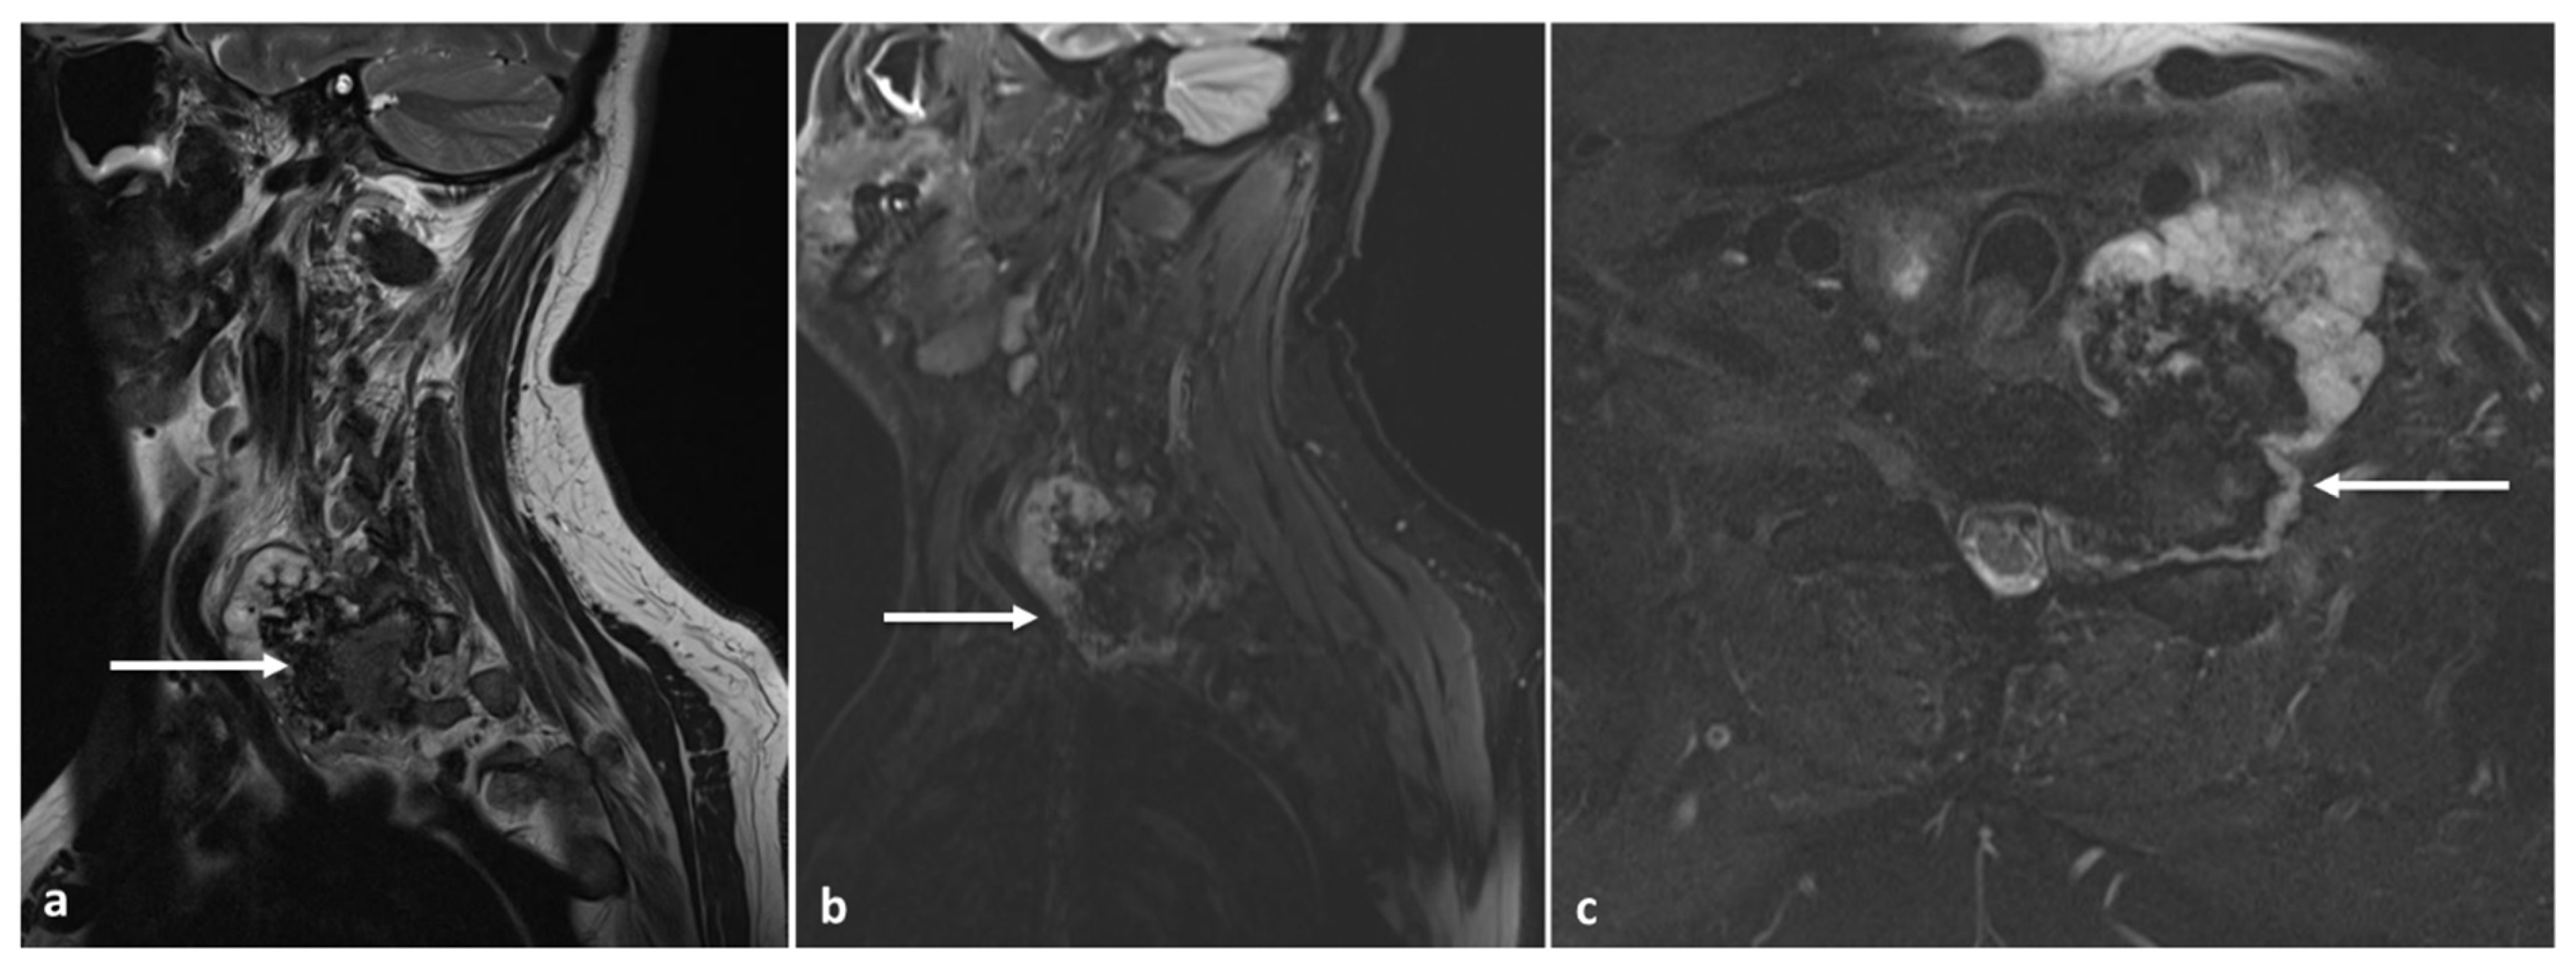

3.6. Chondroblastoma

| Chondroblastoma | Osteolytic lesion. Variable intralesional calcification (chondroid matrix) | Extraosseous soft tissue component |